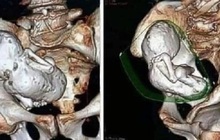

Bác sĩ Chen Qingjiang, Bệnh viện Nhi (Đại học Y khoa Chiết Giang), người điều trị chính, cho biết phim chụp X-Quang phát hiện có nhiều dị vật nhỏ có kích thước bằng hạt đậu nành trong bụng bé gái tên Xiaoyou, 4 tuổi. Dị vật này là những viên bi nam châm.

Các bác sĩ nghi ngờ cô bé đã nuốt những viên bi nam châm nhỏ nhiều lần. Sau khi đến các bộ phận khác nhau trong đường ruột, chúng hút vào nhau và gây ra các lỗ thủng.

"Sau khi tách các viên bi, chúng tôi phát hiện 14 lỗ thủng trong ruột của cô bé. Chúng tôi đã khâu lại và tất cả diễn ra suôn sẻ. Nhưng với cháu bé, ca mổ vẫn là một chấn thương lớn", bác sĩ Chen nói đồng thời cho biết thêm khả năng cao trong tương lai, bệnh nhi phải đối mặt với nguy cơ dính, tắc ruột.